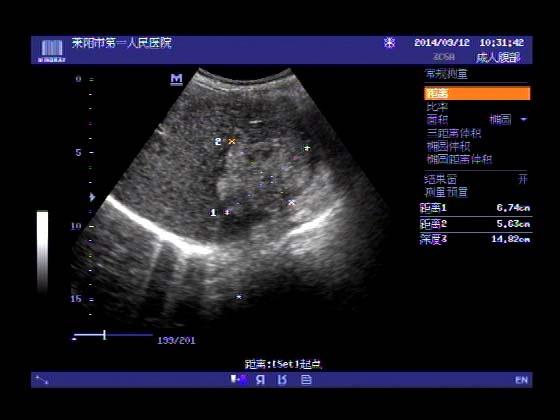

超声入门贴353-----直肠癌伴肝转移

女,66岁